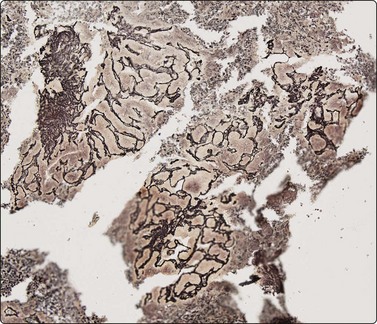

Fig. 10.16 Hepatocellular carcinoma

A reticulin stain on cell block sections may highlight (A) widened trabeculae and/or acinar structures (Reticulin, HP); (B) reduced or absent reticulin (cell block reticulin, HP).

Smears are typically cellular with large fragments, clusters and dispersed cells (Fig. 10.14). Cell groupings are classically trabecular (Fig. 10.15A), particularly in better-differentiated tumors. Acinar arrangements may be seen in up to 40% of HCC (Fig. 10.15B).72 With decreasing differentiation, smaller sheets and single-lying cells become more frequent. A reticulin stain on smears or cell block material may highlight the widened trabeculae and/or acinar structures or the reduced or absent reticulin (Fig. 10.16). Endothelial relationships to HCC cell groups are an integral part of the diagnosis. Endothelial cells of sinusoidal capillaries may traverse (Fig. 10.17) or enclose (Fig. 10.18) trabeculae or separate tumor cell groupings.128 This important diagnostic criterion is diminished and then lost with decreasing differentiation.

The problem of distinguishing well-differentiated HCC (Fig. 10.24) from a benign regenerative nodule, focal nodular hyperplasia or adenoma has been mentioned. Clinical data such as age and sex, presence or absence of cirrhosis, exposure to steroidal hormones and radiological appearances may help to distinguish between these entities. There is considerable risk of overdiagnosing malignancy in regenerative nodules because nuclear enlargement, anisokaryosis, macronucleoli and dissociation may be prominent. Total absence of bile duct epithelium in a cellular smear favors a neoplasm, benign or malignant. The subtle cytological changes may be insufficient to reach a diagnosis of malignancy, and architectural abnormalities are of great importance. If there are endothelial-lined trabeculae or acini, capillary blood vessels which intersect groups of tumor cells, raised nucleocytoplasmic ratios, macronucleoli, many naked neoplastic nuclei, poorly defined cell borders, overall tumor cell monotony with sporadic tumor giant cells, and mitoses, the lesion is probably HCC.39-41,72,79,116-132

Prior to embarking on costly immunotests, a reticulin stain can highlight loss of a normal sinusoidal pattern and shows either widened trabeculae, rounded islands and pseudoglands or just a reduction or total absence of reticulin and distinguish benign from malignant liver lesions (see Figs 10.6 and 10.16).77-79120